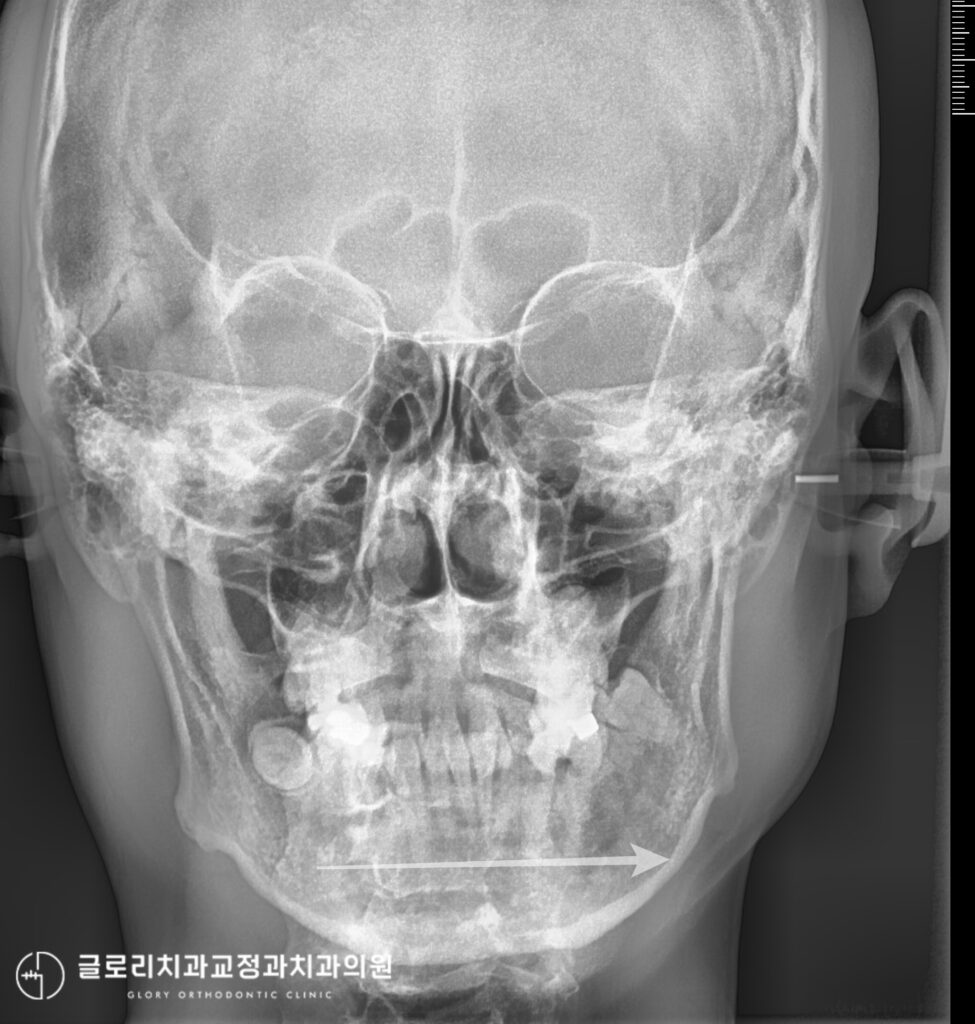

엑스레이를 보면 현재 왼쪽 턱이 좌측으로 약간 편위되어있는 것을 확인할 수 있습니다.